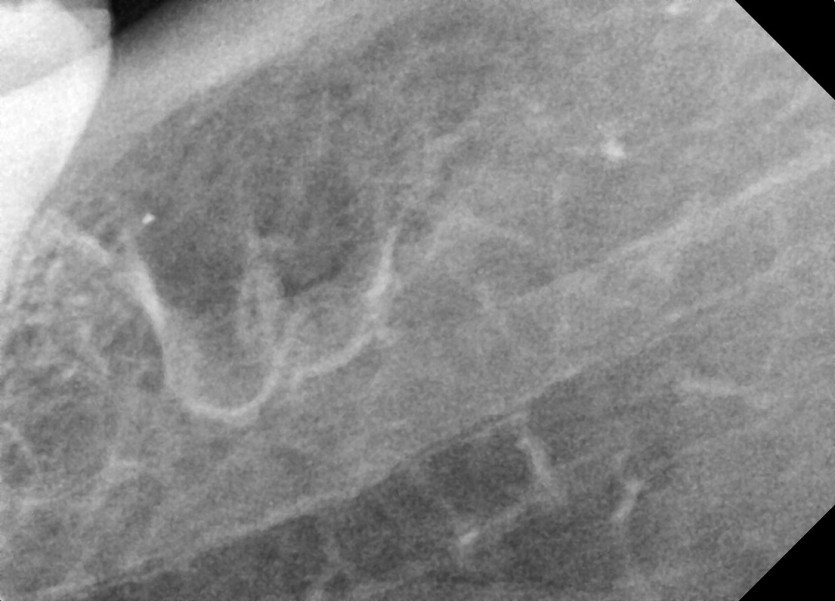

#18,28,38,48 사랑니 발치

구강 외과 전문의가 당일 발치했습니다.